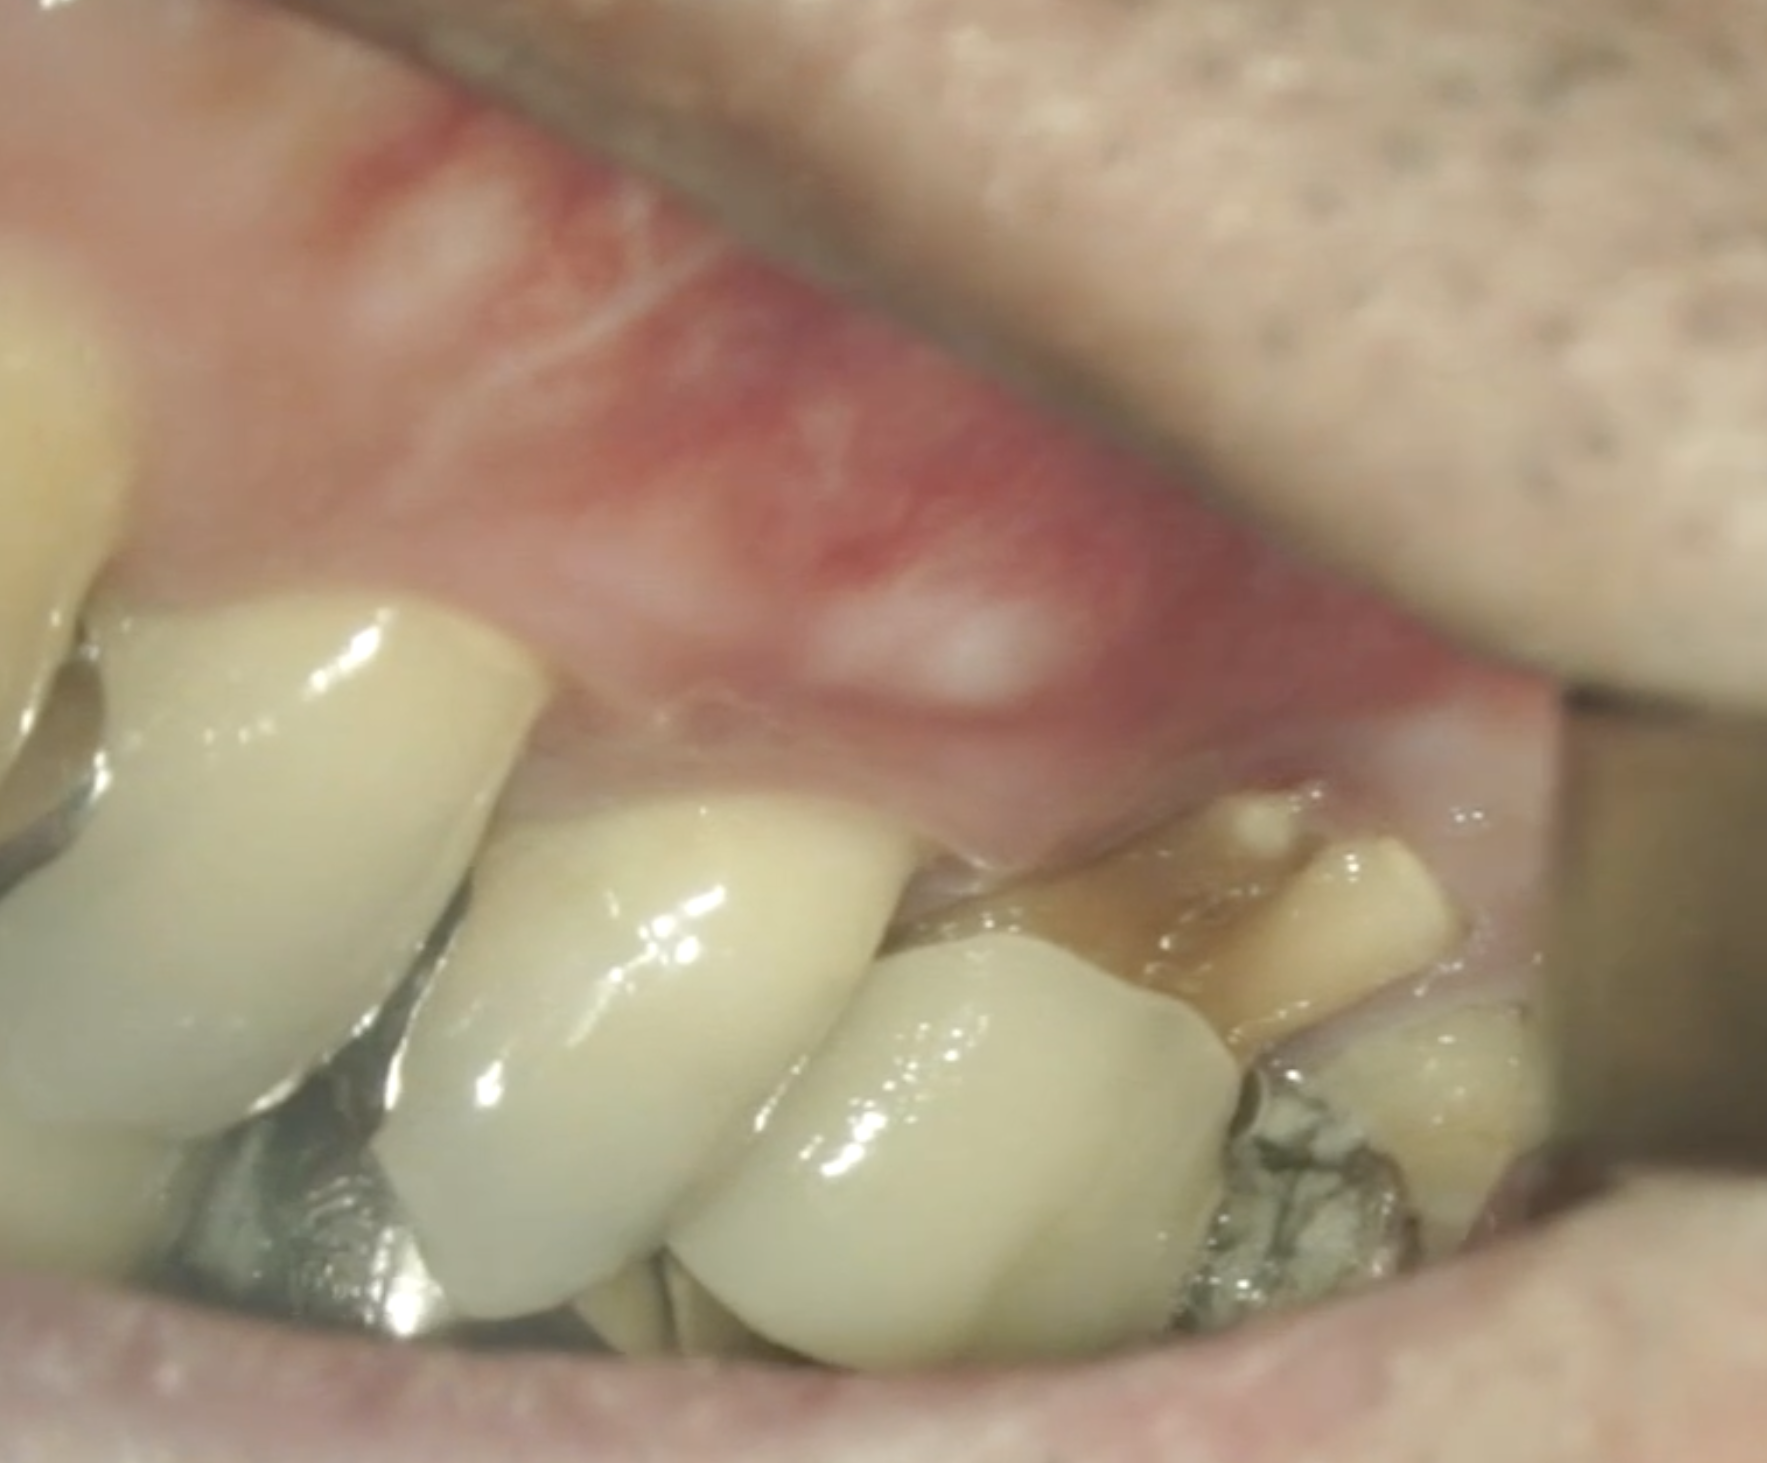

臨床症状は消失したが、口腔内の清掃は悪く歯肉はリセッションしていた。

上顎洞炎は治癒し、Pの歯槽骨はかなり回復したがMB,DBは口腔内に歯根が出てしまっている。

人為的に歯槽骨にダメージを与えて歯根を口腔内に露出させると頬側皮質骨は戻らずリセッションする